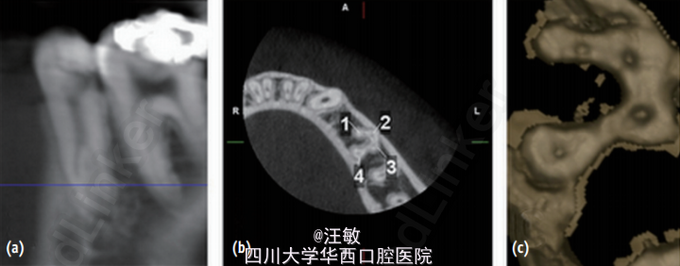

诊断为35牙慢性牙髓炎,拟进行35牙根管。治疗过程中发现35牙为多根管,故使用CBCT和三维重建辅助进行根管治疗

CBCT和三维重建能够帮助临床医生在治疗前充分了解复杂的根管系统,而这些是X线片达不到的。 doi:org/10.5395/rde.2015.40.2.161